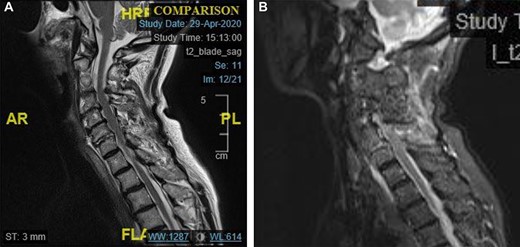

The MRI scan shows that the dislocation had reduced. Fig. 4a demonstrates high signal in the C6/C7 intervertebral disc.

Fig. 4b also demonstrates the injury to the posterior ligament complex at C4 to C7.

(a) Midline sagittal T2 weighted MRI image showing high signal in the C6/7 disc space. (b) Midline sagittal short-t1 inversion recovery weighted MRI image showing high signal in the posterior elements of C4–C7.